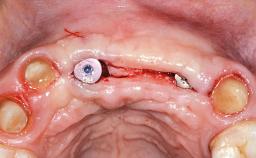

This 20-year-old woman was referred to our department in July 2006. Four months earlier, she had experienced dental trauma to the anterior maxilla when traveling in South America. The emergency treatment included emergency root canal treatment of teeth 12 and 11. Tooth 21 was also subjected to endodontic treatment later. At the initial examination, the patient was not in pain but reported increased mobility of tooth 12. The clinical examination revealed a high smile line, medium thickness of the soft tissue, and rectangular tooth forms. Discoloration of tooth 12 was evident. The periapical radiograph provided by the referring dentist indicated a fracture line at both teeth 12 and 11. A cone-beam computed tomography (CBCT) scan confirmed these fractures. No pathology was found to be associated with tooth 21.

Bone Augmentation Horizontal|Simultaneous

Augmentation Materials Autogenous chips|Xenogenous|Membrane

Bone Volume Deficient horizontally, allowing simultaneous augumentation